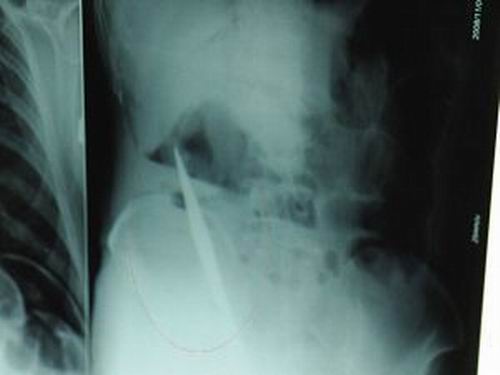

X光片上,尖刀清晰可見。

從男子體內(nèi)取出的尖刀足足有19厘米長。

江蘇銅山一58歲男子因服毒被送到醫(yī)院搶救,可醫(yī)生采取搶救措施后卻發(fā)現(xiàn)效果不佳。后來經(jīng)細(xì)致檢查,醫(yī)生有了個驚人的發(fā)現(xiàn),該男子的體內(nèi)竟然有一把尖刀,醫(yī)生通過手術(shù)將位于其腹部右側(cè)橫結(jié)腸下緣的尖刀取了出來。這把尖刀足足有19厘米長!據(jù)醫(yī)生推測,這把刀應(yīng)該是從肛門推進(jìn)體內(nèi)的,不知男子為何想以如此殘酷的方式結(jié)束自己生命。由于搶救及時,該男子已暫時脫離危險。

昨天(11月6日)上午,記者在徐州礦務(wù)集團(tuán)總醫(yī)院重癥監(jiān)護(hù)室見到了這名男子,目前他雖然已經(jīng)恢復(fù)了意識,但還不能開口說話,需要呼吸機(jī)輔助呼吸。據(jù)醫(yī)生介紹,4日中午12時左右,這名男子因服毒輕生被緊急送到醫(yī)院進(jìn)行搶救,之前,這名男子已經(jīng)在當(dāng)?shù)剜l(xiāng)鎮(zhèn)醫(yī)院進(jìn)行了近20小時的治療,但效果不佳!安∪吮晦D(zhuǎn)院到礦總院時已神志不清,血壓極低,處于休克狀態(tài)!本茸o(hù)人員給男子洗胃、初步處理以后,發(fā)現(xiàn)男子呼吸急促,于是趕緊給他拍片檢查。結(jié)果讓所有的醫(yī)生大吃一驚,竟有一把尖狀異物橫在該男子腹腔內(nèi)!當(dāng)天下午5時30分,輕生男子被推上了手術(shù)臺。經(jīng)過40多分鐘的手術(shù),該男子腹腔被打開,手術(shù)醫(yī)生發(fā)現(xiàn),男子體內(nèi)的金屬狀異物竟然是一把長19厘米的尖刀!